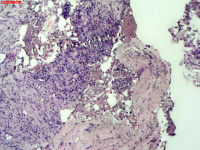

- 右侧胸壁穿刺组织活检

| 性别 | 女 | 年龄 | 81岁 | 临床诊断 | 胸锁关节结核? |

| 一般病史 | 胸部CT示:右肺下叶小结节,建议3-6个月复查,必要时胸外科会诊。左肺上叶多发小斑点、结节影,结核可能。右肺上叶多发点状影。双肺间质性改变。纵隔淋巴结肿大、钙化。右侧胸锁关节见骨质破坏,周围见软组织肿胀。 | ||||

| 标本名称 | 右侧胸壁穿刺组织活检 | ||||

| 大体所见 | B超:体表包块彩超示右侧胸壁混合回声包块,右侧胸壁低回声区,CDFI示:其内未见明显血流信号。 | ||||